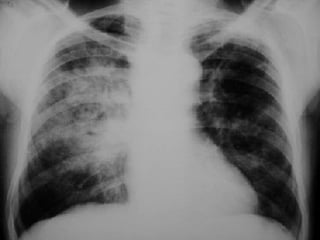

RX TORAX NEUMONIA DEL ESPACIO AEREO:  infiltrados alveolares con broncograma aéreo. INFILTRADO INTERSTICIAL:  patrón reticulonodulillar.

RX TORAX NEUMONIADEL ESPACIO AEREO: infiltrados alveolares con broncograma aéreo. INFILTRADO INTERSTICIAL: patrón reticulonodulillar.